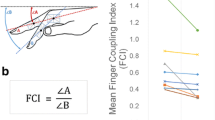

Participants were seated while holding the dynamometer upright, with their elbow bent to approximately 90°, without forearm support. The peak isometric grip and pinch strength (Newton) for two trials was averaged for each hand. In this study, we only considered the dominant hand. See Fig. 1.

Experimental set-up. A Each subject underwent routine neurophysiological assessment evaluating motor (MEP) and somatosensory-evoked potential (SEP) latency and amplitudes, and transcranial magnetic stimulation (TMS) protocols evaluating motor (resting motor threshold, RMT; active motor threshold, AMT; short-interval intracortical inhibition, SICI; long-interval intracortical inhibition, LICI; short-interval intracortical facilitation, SICF; intracortical facilitation, ICF) and sensorimotor cortex (short-latency afferent inhibition, SAI) excitability. Afterward, behavioural protocols were applied to assess the sensorimotor coordination (B) and strength aspects (C) of hand functionality. B Sensorimotor coordination tasks consisted of the 9 Hole-Peg-Test (9HPT) and finger movement analysis with an engineered glove, evaluating five parameters: (i) rate at spontaneous velocity; (ii) rate at maximal velocity; (iii) Touch Duration (TD) at 2 Hz; (iv) Inter Tapping Interval (ITI) at 2 Hz; (v) % Correct sequences. C The hand strength was assessed by handgrip and three-point pinch tests

Sensorimotor coordination was assessed at baseline (T0) and after 1 year (T12) by the conventional 9HPT and by the analysis of finger movements with a dedicated engineered glove [5], Fig. 1. As for 9HPT, both hands were tested twice—in two consecutive trials of the dominant hand, followed by two consecutive trials of the nondominant hand—to determine the time taken to complete the test. There was a 300-s time limit per trial. In this study, we only considered the dominant hand.

Finger motor performance was measured by means of a sensor-engineered glove on the dominant hand (GAS, ETT S.p.A., Italy) [5]. All participants were asked to perform self-paced (i.e., right hand at spontaneous velocity), maximal velocity, and metronome-paced (right hand at 2 Hz) repetitive sequences of finger opposition movements (thumb to index-medium-ring-little fingers). Touch Duration (TD) at 2 Hz was computed as the contact time between the thumb and another finger, while Inter Tapping Interval (ITI) at 2 Hz was defined as the time interval between the end of a thumb-to-finger contact and the beginning of the subsequent contact in the finger motor sequence. An eyes-closed paradigm was chosen to exclude possible confounding effects attributable to the integration of acoustic and visual information, and to prevent patients from compensating for possible sensorimotor impairments by visual inspection. Data were acquired at 1 kHz by means of a data acquisition board (USB-1208FS, Measurement Computing, USA). An ad hoc software tool generated the acoustic pacing signal and recorded the occurrence of each tone and of the corresponding finger touch in the motor sequence. Before starting the recording session, all subjects practiced the task at their own spontaneous pace; training ended generally within 2 min when they were able to perform the finger motor sequence without errors. The testing session included three randomly presented 60-s trials (one per condition).